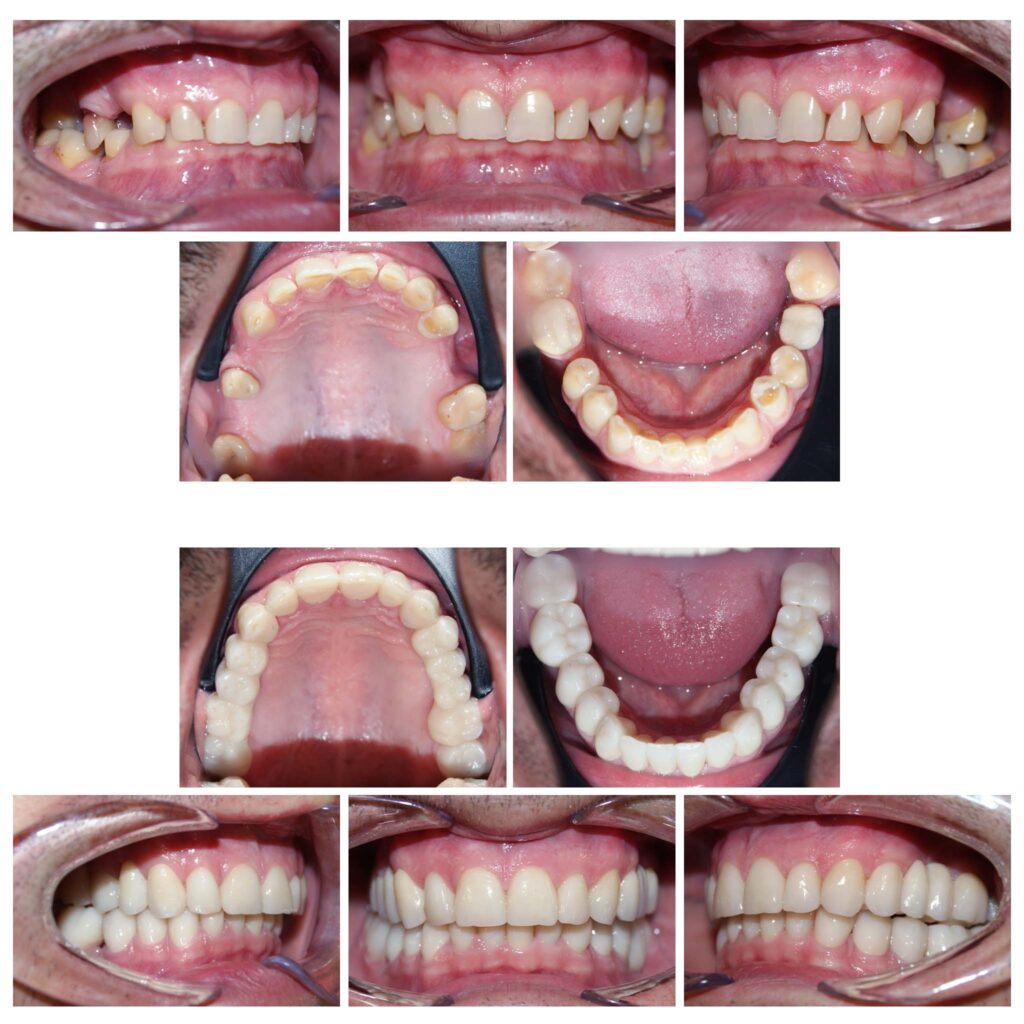

Reabilitare orală complexă cu redimensionarea dinților cu grad accentuat de uzură. A fost necesară o soluție de provizorat de 6 luni de zile în care am verificat dacă pacientul se poate adapta cu înălțarea ocluzală propusă de noi. Am realizat tratamente de canal și reconstituiri atât pentru înălțarea dinților, cât și pentru tratarea proceselor infecțioase active. Rezultatele sunt remarcabile atât din punct de vedere funcțional cât și estetic